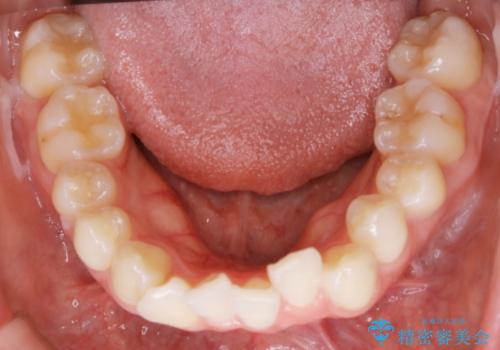

- 歯のガタつきと出っ歯感を治したいとの主訴でご来院され、ハーフリンガル装置を希望なさったため、検査を行ったうえで上下左右4番目の歯を抜歯し歯列を内側に引っ込めつつ叢生の改善を行うこととなりました。

ハーフリンガルとは上顎を裏側、下顎を表側のワイヤー装置で治療する場合をいいます。

フルリンガル(上下とも裏側)で治療するよりも費用が抑えられ、治療期間も伸びにくい傾向にあります。また、下顎の舌側に装置がないおかげで口内炎や発音障害もフルリンガルに比べて少ないとされています。

ただし、上下とも表の装置に比べると治療期間・費用共に劣る傾向にあります。